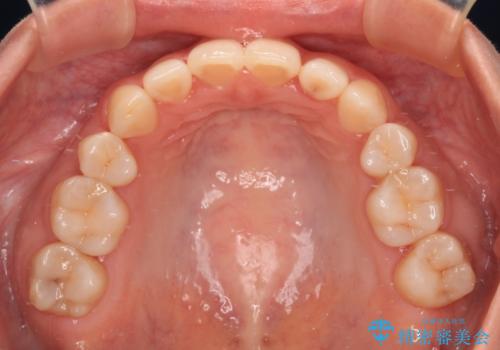

口元の突出感のない、すっきりとした仕上がりとなりました。